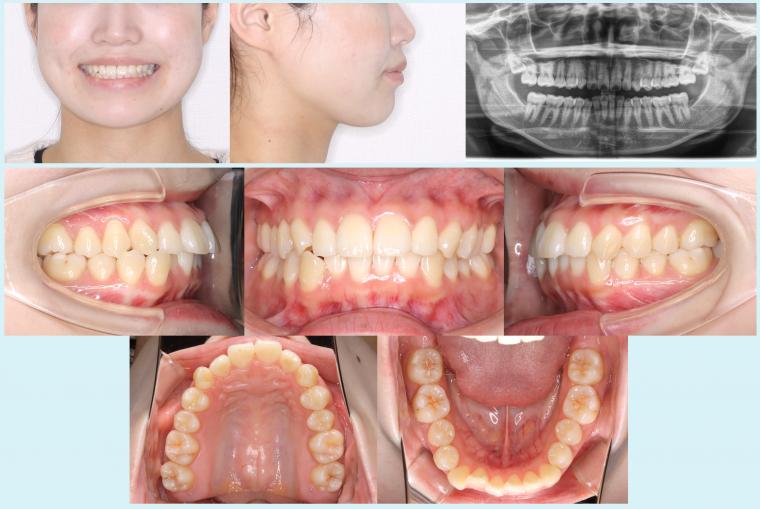

#45 軽度叢生を治療した症例